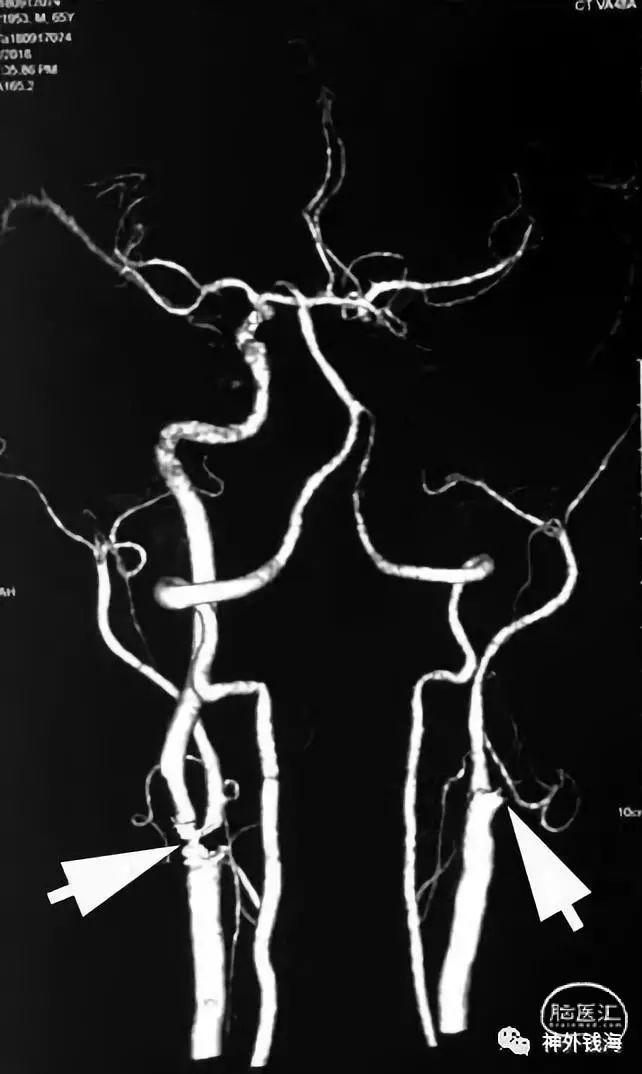

从患者的CTA看,供应脑部最重要的一根血管-右侧颈内动脉已经闭塞。但是颅内血管看起来还可以。左侧箭头示左侧颈内动脉重度狭窄,右侧箭头示右侧颈内动脉已经闭塞。